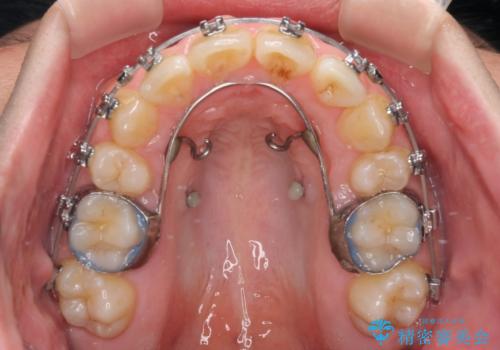

マウスピース矯正でもワイヤー矯正でも対応可能でしたが、患者様の希望によりワイヤー装置による矯正治療を行うこととしました。

ワイヤー矯正ということで、上顎大臼歯を後方に移動するための補助装置を併用して、積極的に前歯を引っ込めていくこととしました。

上顎歯列全体がスムーズに後方移動でき、1年で治療を終えることができました。